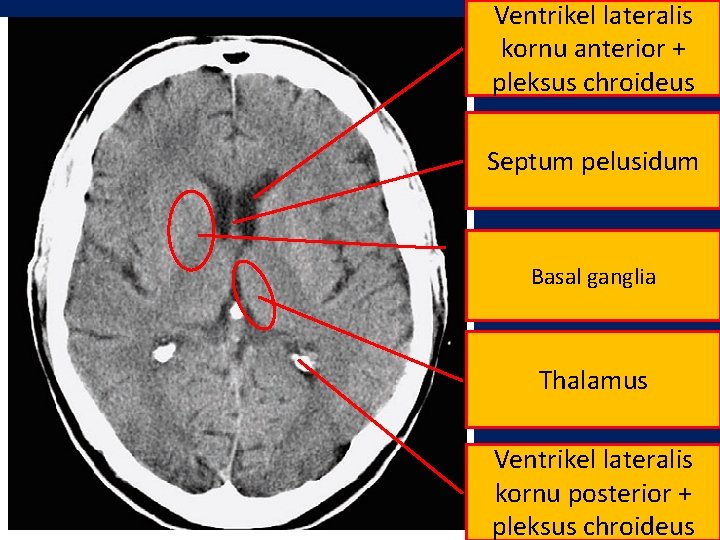

Ventrikel lateralis kornu anterior + pleksus chroideus Septum pelusidum Basal ganglia Thalamus Ventrikel lateralis kornu posterior + pleksus chroideus